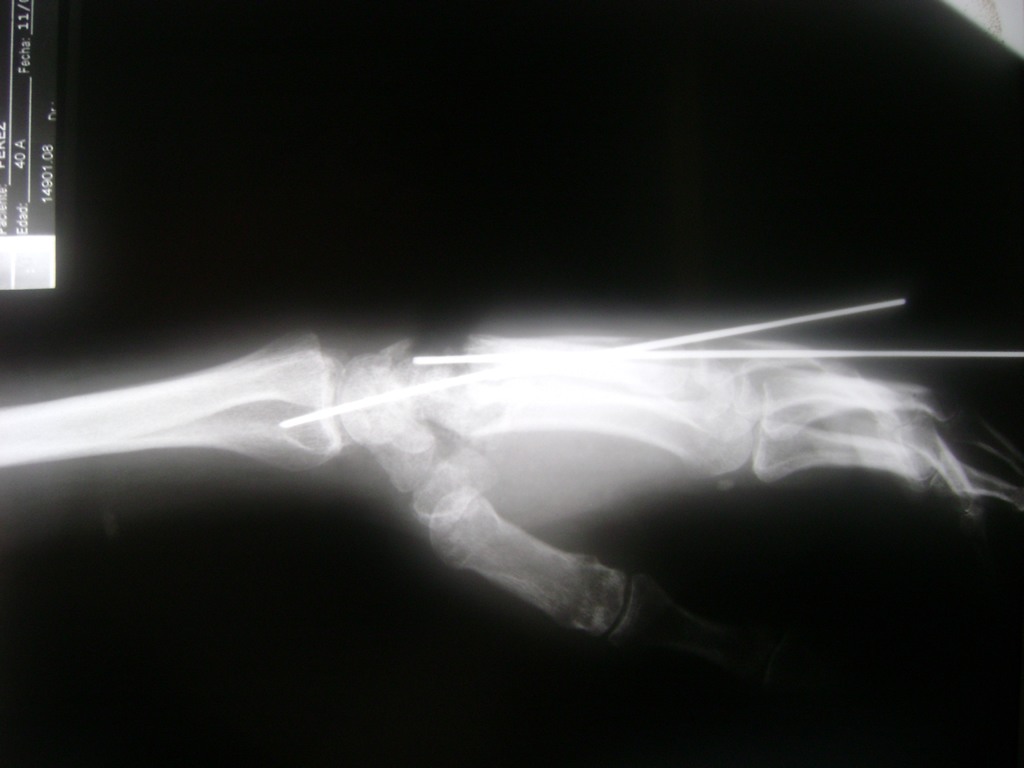

Cirugía de Muñeca y Mano

Los procedimientos más comunes en cirugía de la mano son aquellos destinados a reparar traumatismos, incluyendo lesiones de tendones, nervios, vasos sanguíneos, y articulaciones; huesos fracturados; y quemaduras, cortes, y otros daños de la piel.